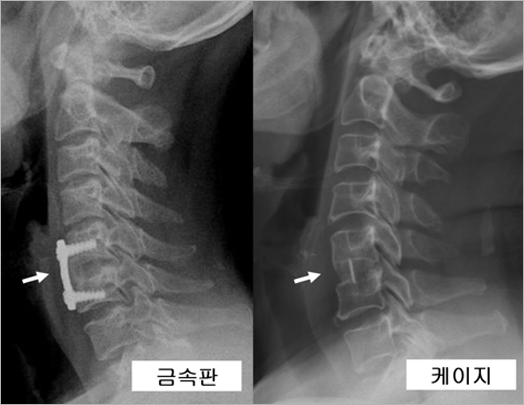

| 물론 추간판을 제거한 후 반드시 인공디스크를 사용해야 하는 것은 아닙니다. 인공디스크가 개발되기 이전에는 추간판 공간에 자신의 골반에서 채취한 작은 뼈조각이나 동종골(다른 사람의 뼈), 혹은 인공뼈를 채워 넣어 위 아래 경추체를 통뼈로 만드는 유합술을 시행해 왔습니다. 이러한 유합술은 수많은 연구를 통하여 수술후 단기(수술 직후) 및 장기(수술후 최소한 수년-십 년 이상 경과 후) 결과가 매우 우수하다고 입증된 수술법입니다. 최근 인공디스크 삽입술이 등장하면서 일반인들에게는 유합술이 마치 구식 치료로 비추어질지도 모르겠지만 사실은 전혀 그렇지가 않습니다. "목디스크"에서 추간판 제거술후 시행하는 유합술은 현재까지도 가장 좋은 치료법(외과의사에게는 흔히 "gold standard"라 불립니다.)으로 알려져 있습니다. 하지만 이 수술법은 논란의 여지가 되고 있는 몇 가지 단점이 있기 때문에 이러한 단점을 보완하기 위해 인공디스크가 개발되어 유합술을 대체할 하나의 수술적 치료 옵션으로 등장하게 된 것입니다. 유합술도 삽입되는 뼈의 종류와 기구에 따라 많은 종류가 있지만 현재 우리나라에서 가장 흔히 사용되는 방법은 크게 두 가지로, 첫째 뼈의 삽입 후 금속판과 나사못으로 고정하는 방법, 둘째 뼈를 담은 케이지만을 삽입하는 방법이 있습니다(그림 6). 금속판을 사용하는 경우는 추간판이 제거된 공간에 환자 자신의 뼈, 다른 사람의 뼈, 인공뼈 조각을 채운 후 이것들이 앞으로 빠져나오지 않도록 경추체의 앞면에 금속판을 대고 나사못을 위 아래 경추체에 삽입하여 고정하게 됩니다. 케이지란 것은 속이 빈 튜브 형태의 삽입물을 총칭하는 용어로서 중앙의 빈 공간에 마찬가지로 자신의 뼈, 다른 사람의 뼈, 인공뼈 등을 채운 후 삽입하게 됩니다. 보통 케이지 위 아래면에는 척추체의 단면과 접촉하여 쉽게 빠져나오지 않도록 톱니나 작은 못이 돌출되어 있어 한, 두 마디의 추간판 수술시 단독으로 사용하여도 크게 문제가 되지 않습니다. 그림 7은 이러한 두 가지 방법으로 각각 유합술을 시행받은 환자의 엑스레이를 보여주고 있습니다. 해당 부위의 추간판 공간을 자세히 관찰해 보십시오(화살표). 그림 2에서 보이던 것처럼 추간판 공간이 비어있지 않고 뼈조각으로 채워져 있으며 위 아래 척추체가 이것에 의해 단단히 연결되어 하나의 뼈가 되었습니다. |

| • 그림 6 금속판과 케이지 |

![]() |

| • 그림 7 금속판과 케이지를 이용한 유합술 |